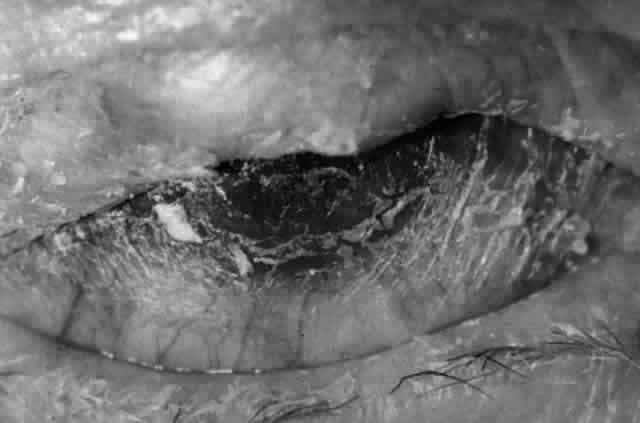

Pemphigus can be differentiated from bullous pemphigoid and from cicatricial pemphigoid on histologic and immunologic bases. Whereas the bullae in pemphigus are intraepidermal, those occurring in bullous pemphigoid and in cicatricial pemphigoid are subepidermal, between epidermis and dermis, or between mucosa and submucosa. Acantholysis is not present in the latter two conditions.5 In bullous pemphigoid and in cicatricial pemphigoid there are tissue-fixed immunoglobulins in the subepidermal basement membrane zone (Fig. 2).11 This is in contrast to the interepidermal fixation of antibodies (Fig. 3) seen in pemphigus (Table 1).

The conjunctival involvement in pemphigus may lead to symblepharon as a result of the formation and rupture of small vesicles. This does not, however, lead to progressive scarring and blindness, as is so often the case in cicatricial pemphigoid (Fig. 4).13

Clinically, the ocular disease in cicatricial pemphigoid (OCP) may present unilaterally in the form of a chronic, recurrent catarrhal conjunctivitis, but it eventually becomes bilateral. Subepithelial fibrosis is characteristic of stage 1 of OCP (Fig. 7). Stage 2 shows fornix foreshortening (Fig. 8), and symblepharon formation is the hallmark of stage 3 (Fig. 9). Stage 4, end-stage disease, is characterized by ankyloblepharon and surface keratinization (Fig. 10). Obstruction of the lacrimal ductules and meibomian gland ducts eventually produces an unstable tear film and progressive sicca syndrome, but it is to be emphasized that OCP is not a dry-eye syndrome until late in the disease course.20 Trichiasis and entropion occur because of the subepithelial fibrosis, with eventual keratopathy, corneal neovascularization, and corneal ulceration and scarring.20